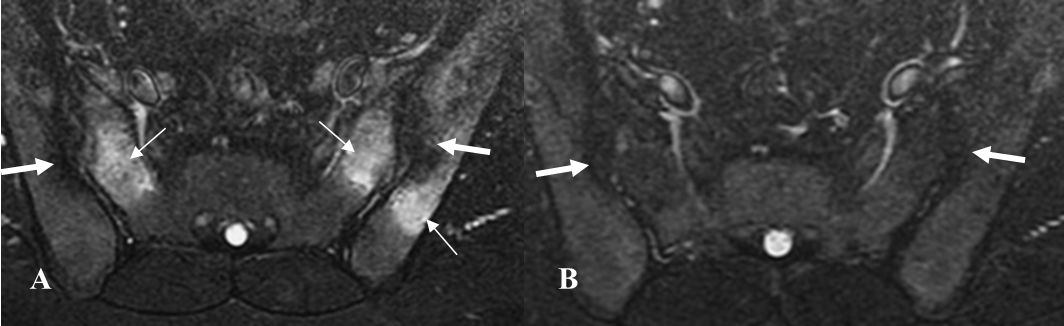

Fig 58 A. Espondilitis anquilosante.

A y B: RM axial en STIR. Edema trabecular en los alerones del sacro a nivel bilateral y el iliaco izquierdo. (Flechas delgadas). Con tratamiento y en un control realizado 2 años después, han desaparecido los cambios inflamatorios agudos. En ambas imágenes hay lesiones de evolución crónica, sobre los iliacos. (Flechas gruesas).

Fig 58 B. Espondilitis anquilosante.

RM coronal en STIR. Lesiones agudas bilaterales, identificadas en el mismo corte.

Fig 58 C. Espondilitis anquilosante.

A y B: RM coronal en STIR. Lesiones agudas bilaterales, en A. Si solo se encontrara la lesión del lado izquierdo, esta tendría que verse en 2 cortes consecutivos, para ser considerada positiva. (Flechas delgadas).